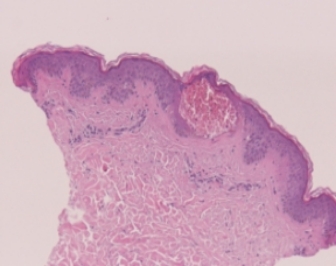

Clinically Proven LIOB Effect for Skin Rejuvenation

(Acne Scar, Pore Tightening, Skin Laxity, Fine Wrinkle etc.)

100x

Courtesy of J.B Lee M.D

200x

400x

LIOB

Laser Induced Optical Breakdown